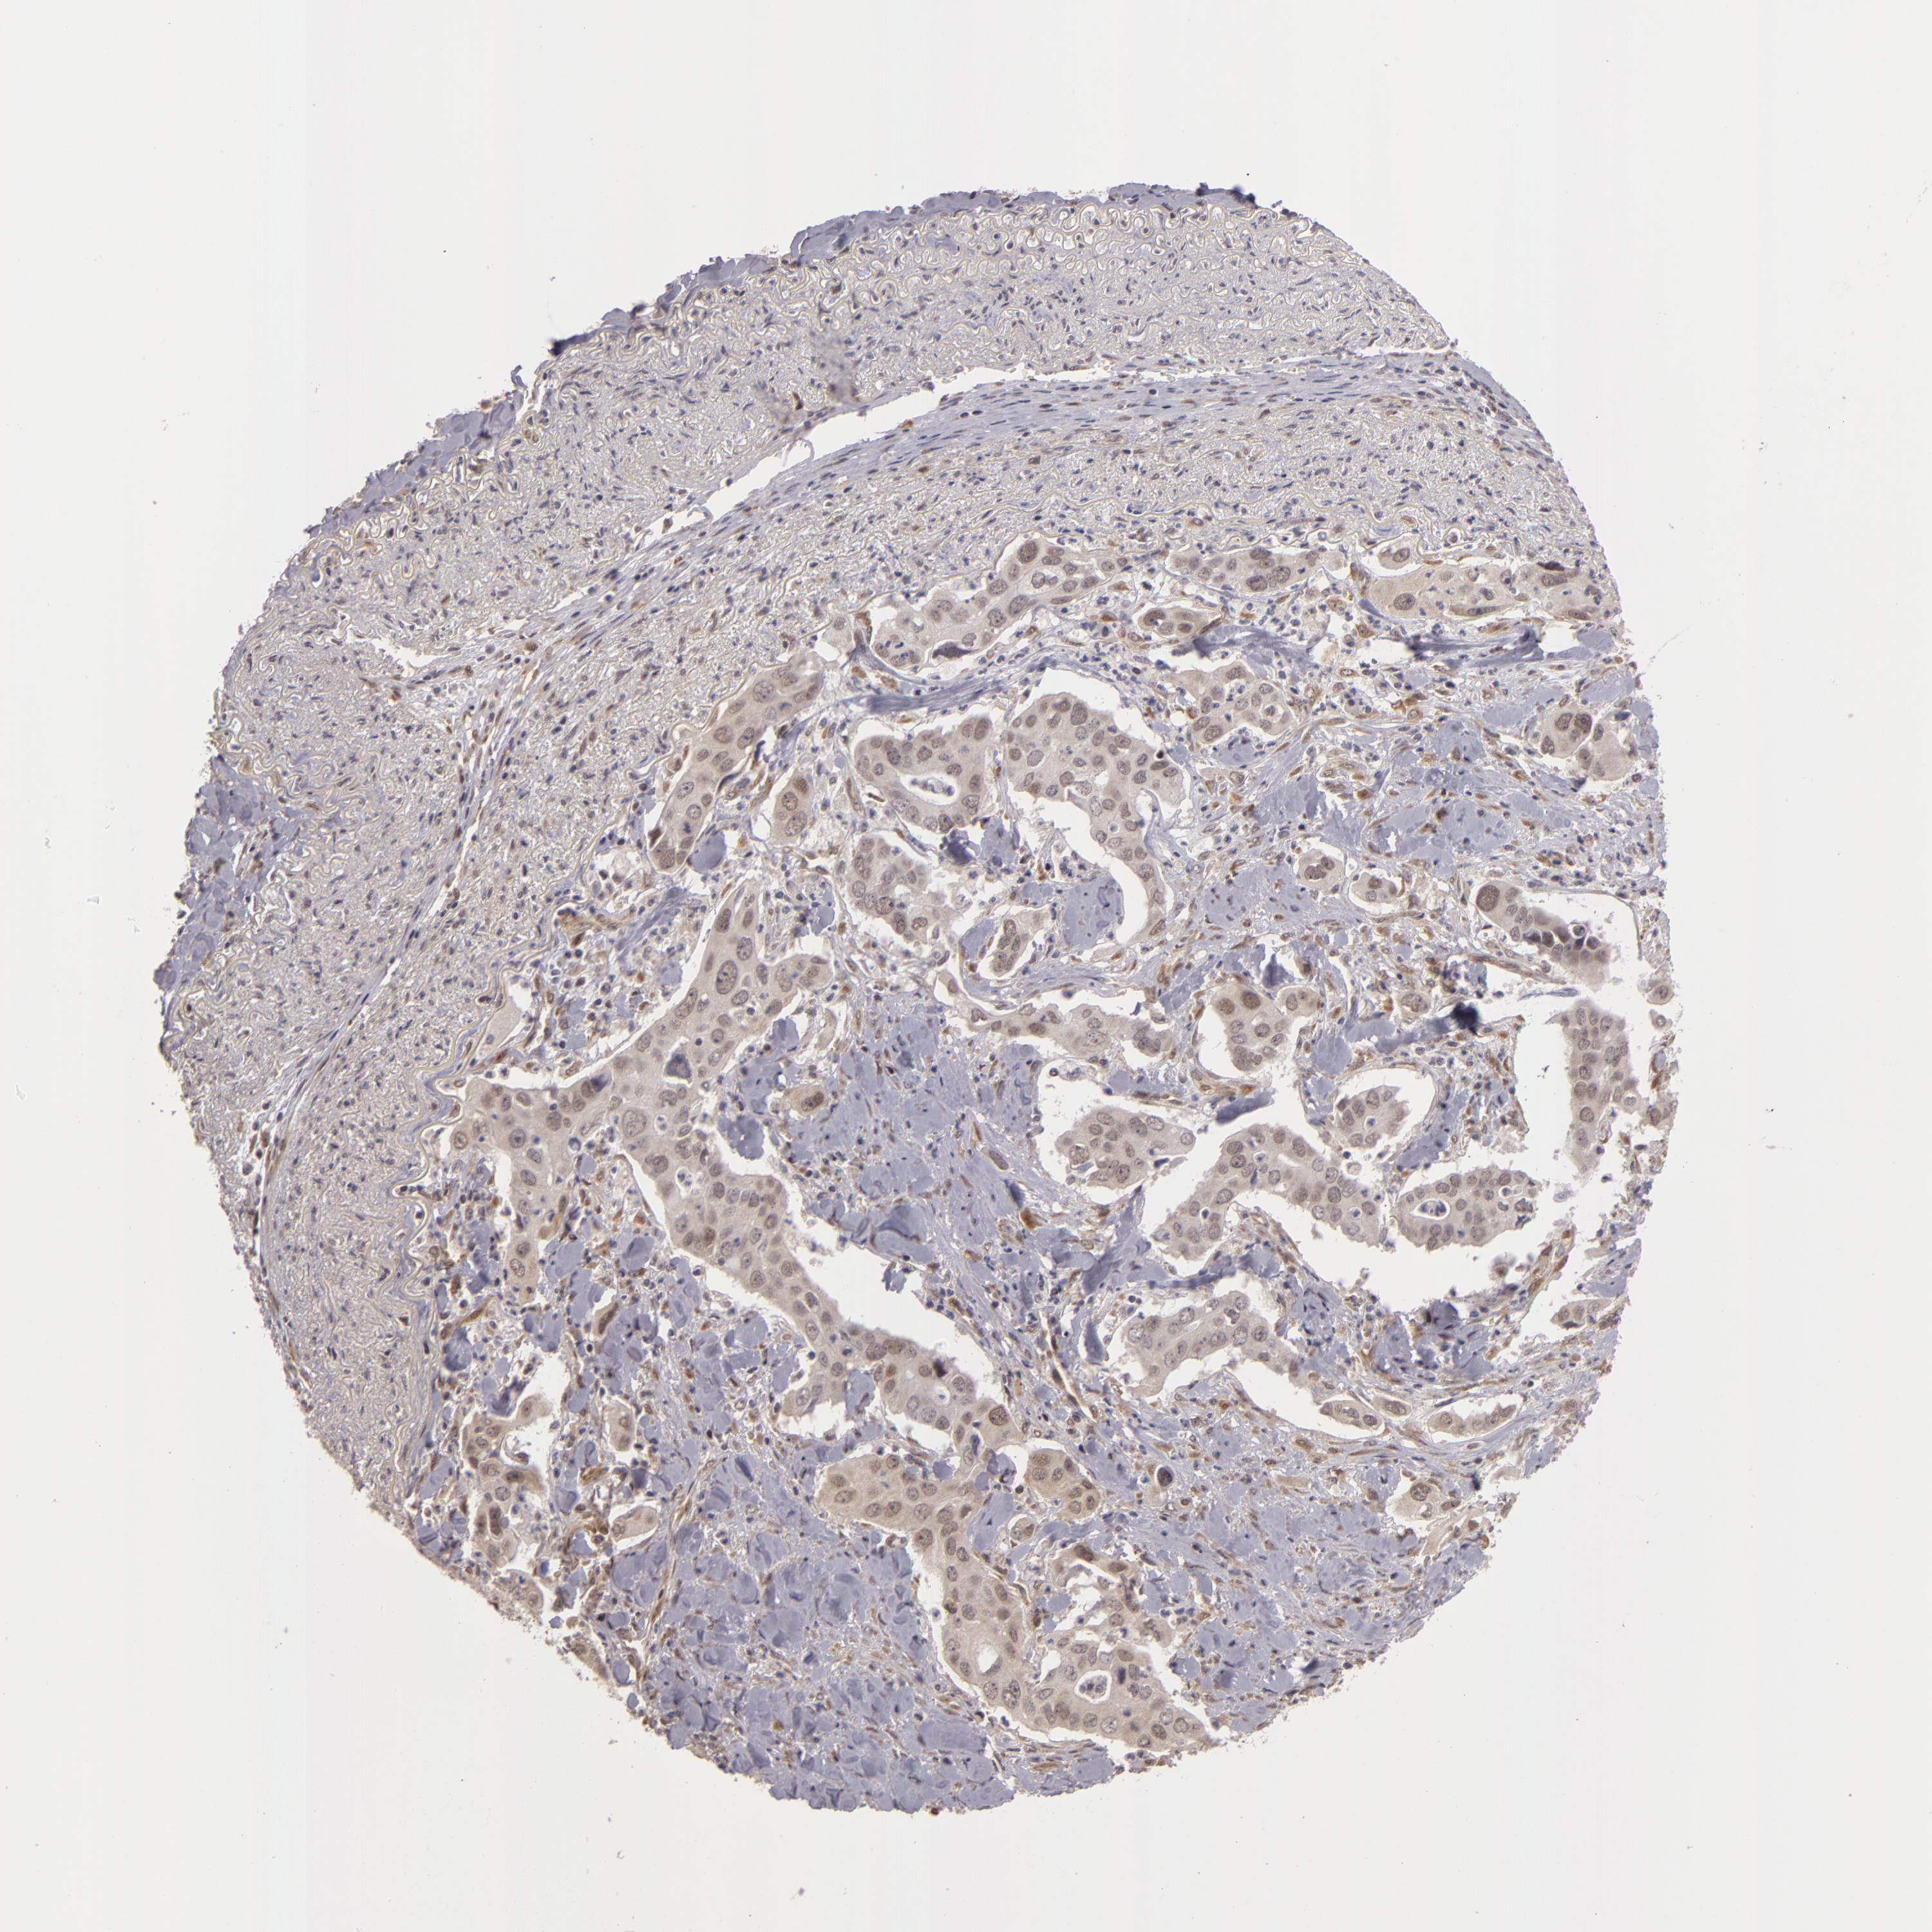

CANCER LUNG CANCER Show tissue menu

Lung cancer

Human cancer